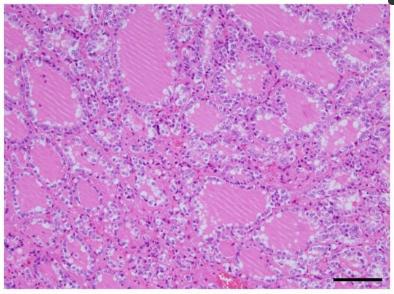

对其进行了病理解剖。甲状腺的大体检查结果包括弥漫性增大(重量675g,大小14cm× 6cm,正常重量20~30g,正常大小5cm× 2.5cm)和甲状腺对上气道的压迫性收缩(图4)。甲状腺的组织学发现显示甲状腺滤泡生长增加和胶质吸收增加,提示甲状腺机能亢进状态(图5)。

没有明显的恶性发现。关于其他大体发现,双侧主肺动脉扩张,肺重量增加(右1030 g,左1110 g,女性右肺正常重量200~500 g,左肺正常重量200~400 g)。右心室和心房也扩张了。观察到明显的右心肥大。这些发现提示慢性肺动脉高压。死亡原因被认为是由于持续静脉注射依前列醇治疗IPAH导致甲状腺肿大导致气道狭窄导致呼吸衰竭。

图5、甲状腺的组织学发现